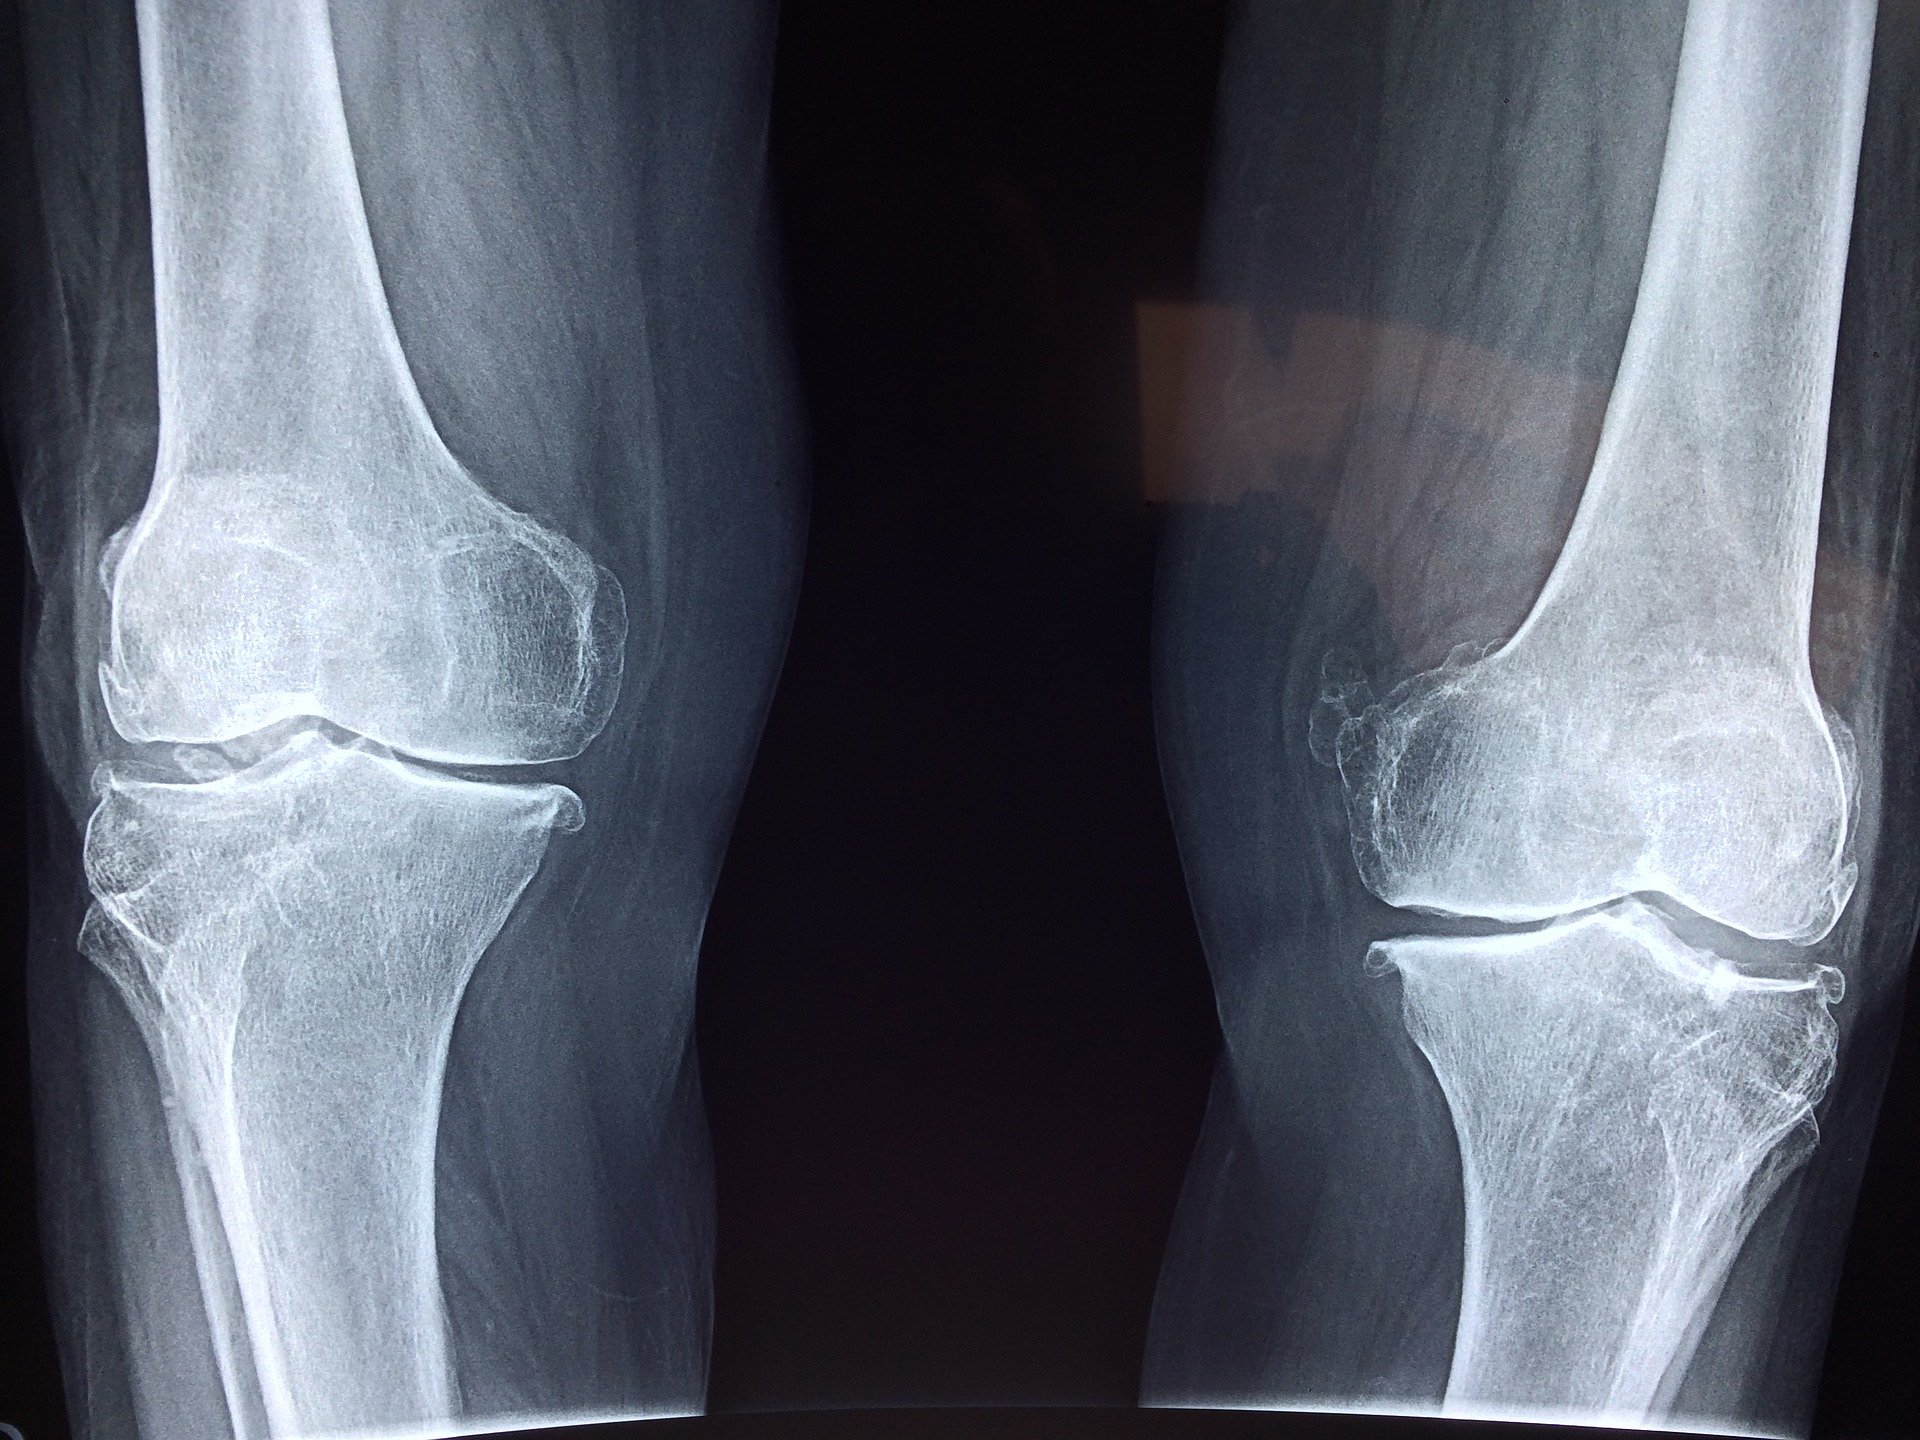

Opuchnięte kolano może wiązać się z różnymi problemami. Zawsze warto udać się z tym do lekarza, który oceni, co konkretnie się dzieje i co można na to zaradzić.